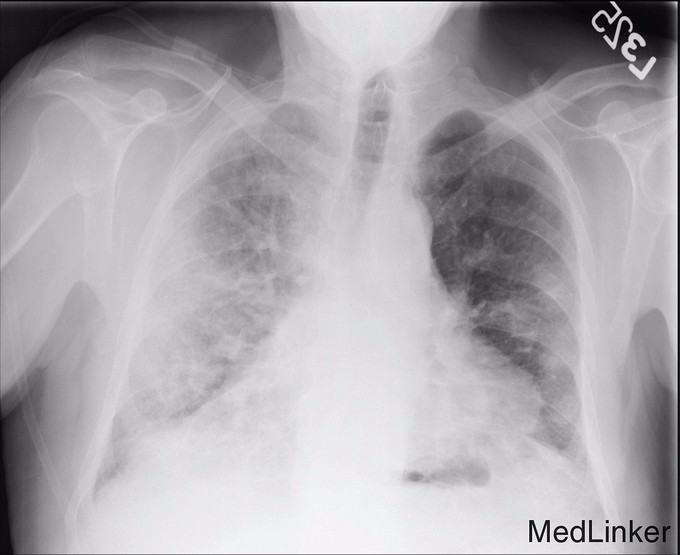

入院前5-6周胸部X线示双侧肺片団影(图1),怀疑为社区获得性肺炎,给予阿奇霉素和莫西沙星,症状无明显改善。入院后体检发现患者有中度呼吸窘迫,血压171/88 mmHg,血氧饱和度86%。查体:患者有双侧哮鸣音及啰音,余未查见特殊。白细胞计数正常,胸部X线提示右下肺和左肺中央显著地恶化(图2)。胸部CT提示弥漫性肺病变,右侧少量胸腔积液,胸内,颈下淋巴结肿大(图3)。